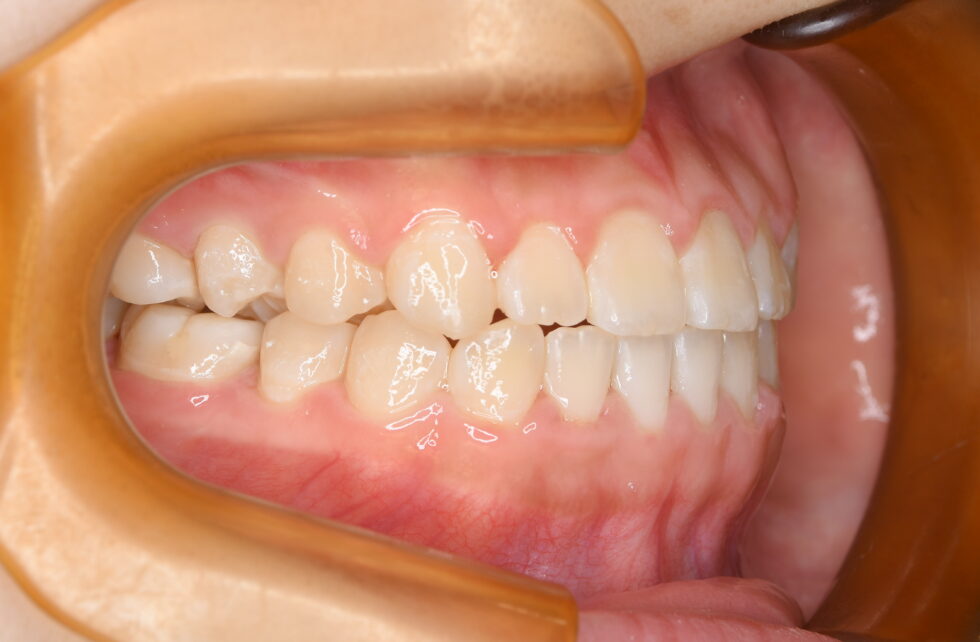

初診時年齢14歳の女子 上顎右側第二小臼歯の埋伏を主訴に遠方の歯科医院より紹介来院した。

埋伏している小臼歯は歯冠を遠心に向けて埋伏しており口蓋側面が歯肉から少し露出していた。また、歯列内に移動するための余地も5㎜程度不足しており、この余地を作ることと、埋伏歯の牽引を同時に行うことを目標に治療を開始した。近心を向いていた歯根の移動に時間を要し、頬舌側を逆転する形で歯列内に配列した。従って、頬側側にある口蓋側咬頭の咬合状態は甘いが、口蓋側にある頬側咬頭は咬合接触を得ることができた。動的治療3年3か月間で保定へ移行した。